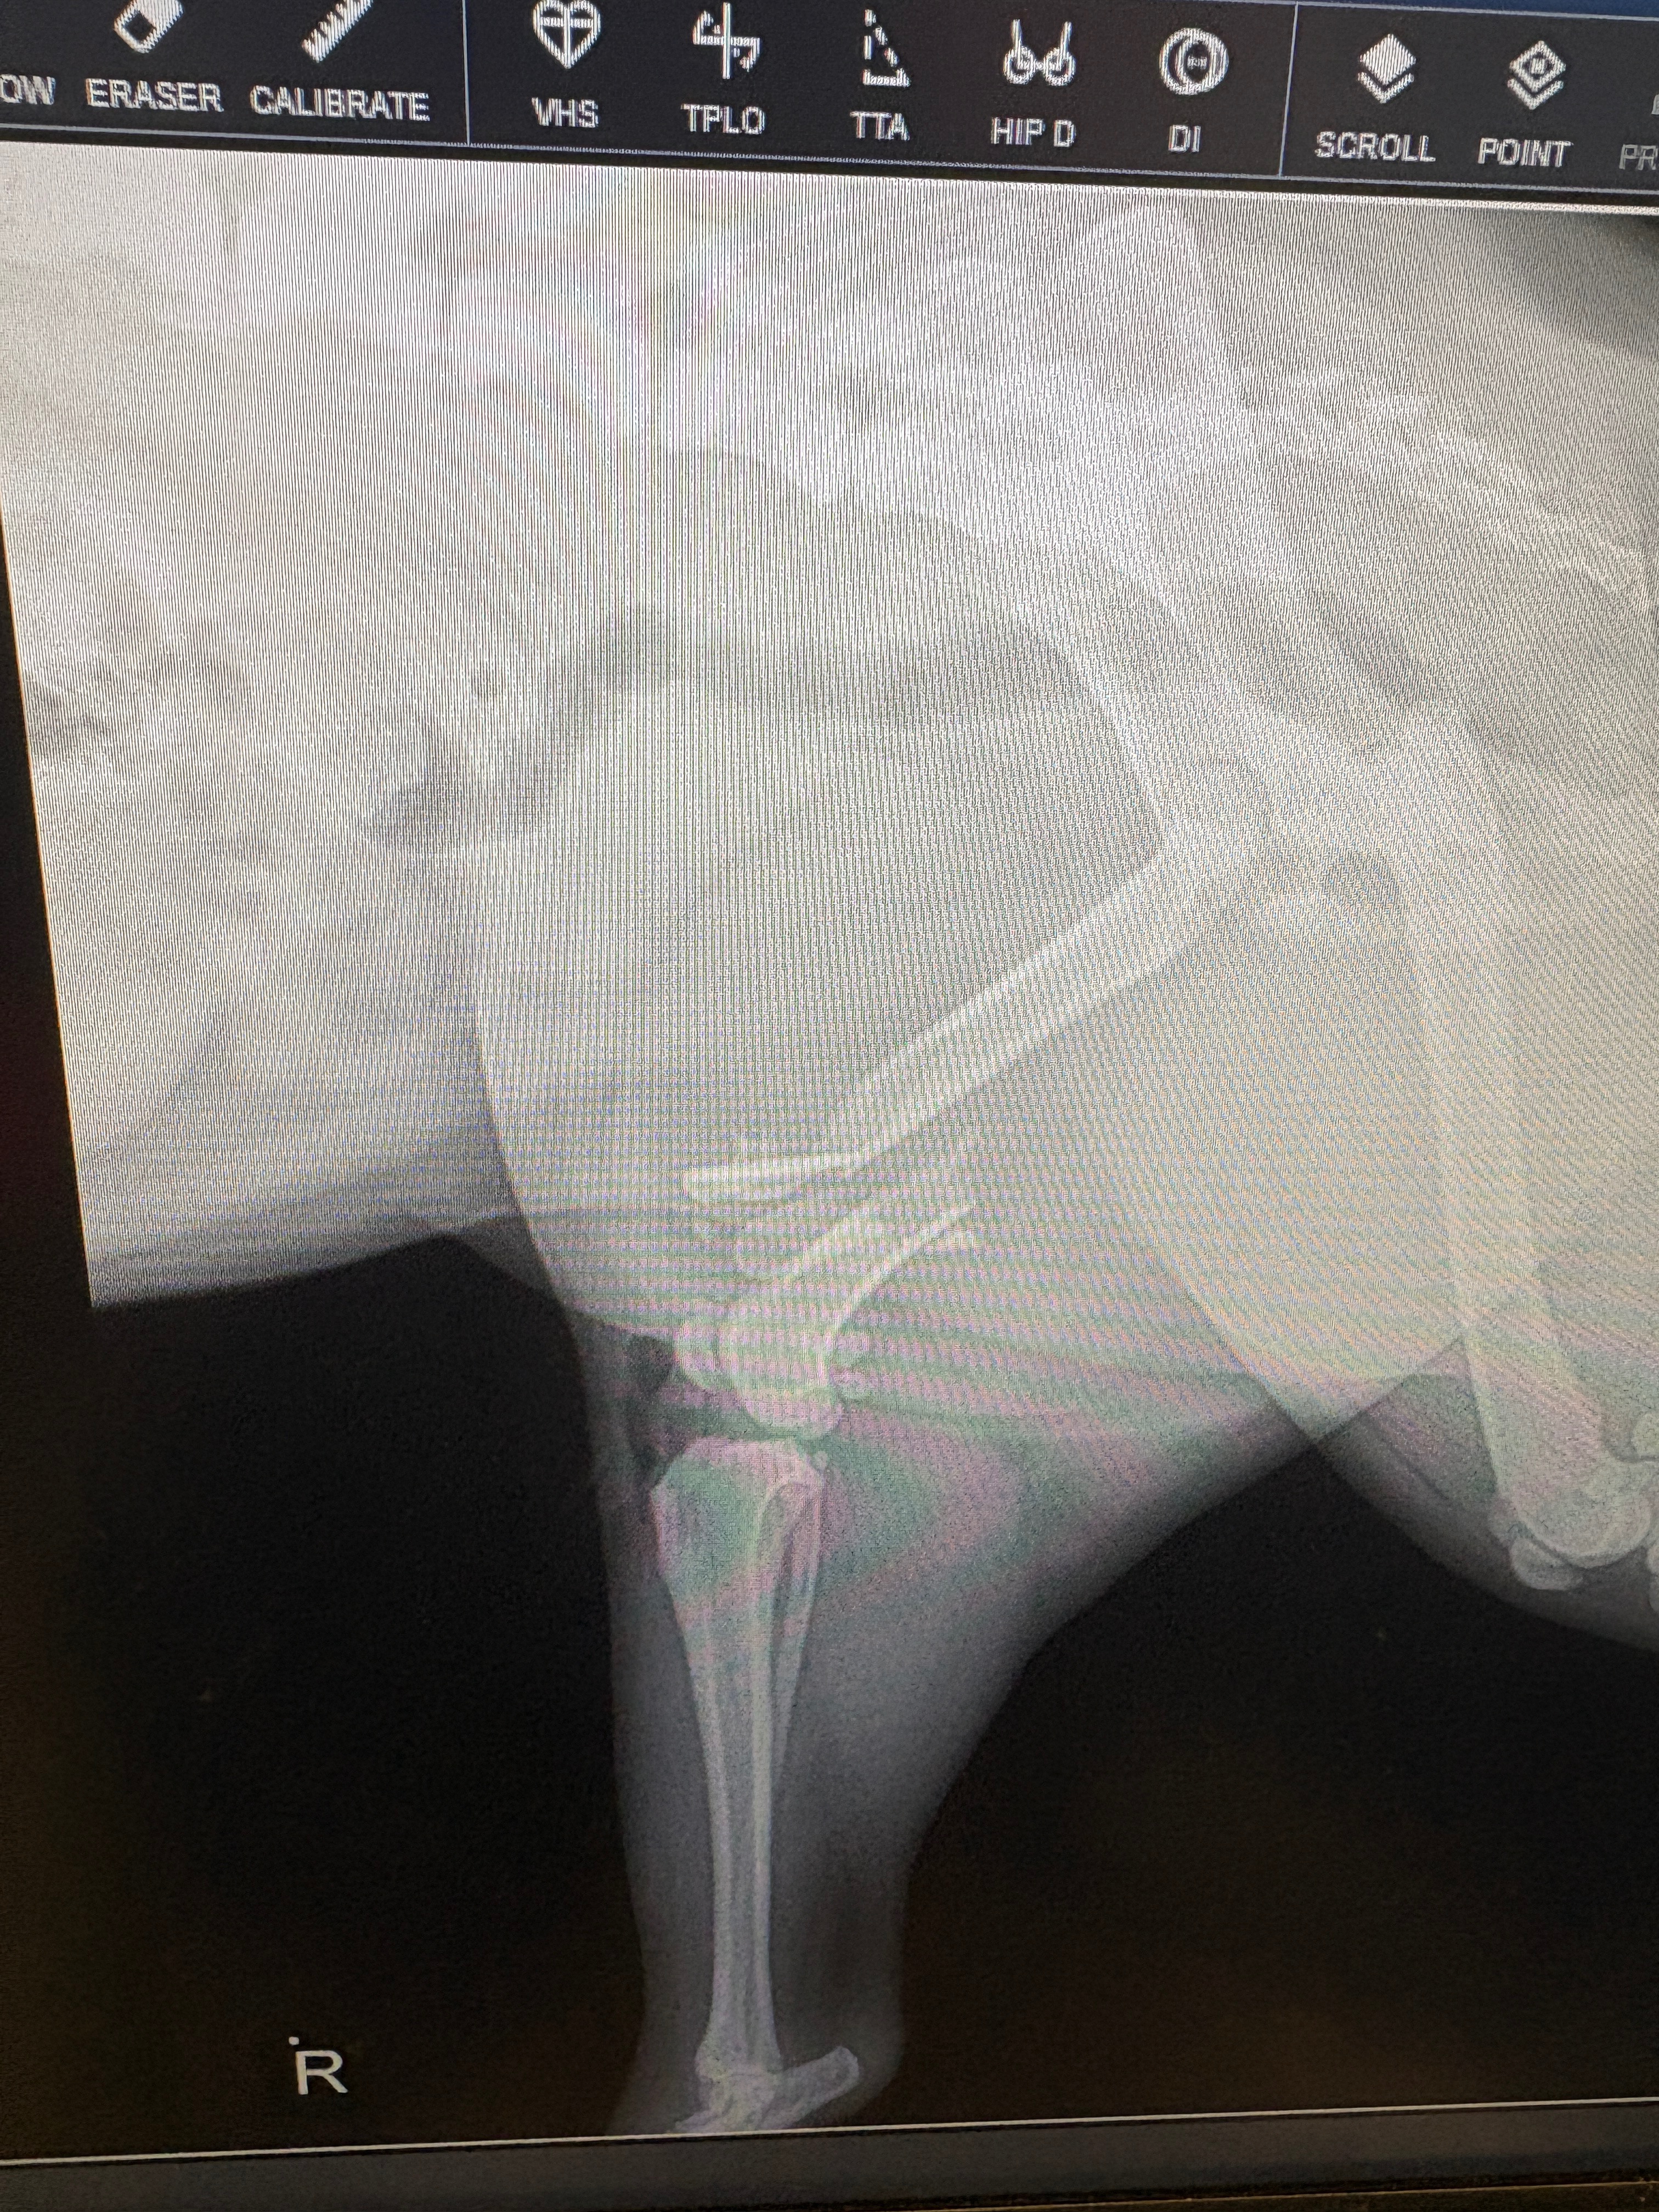

Our sweet girl now has a compound fractured femur and needs urgent surgery to save her leg and allow her to walk again. The veterinary team says the procedure will cost $10,894 — an amount far beyond what we can afford. Without this surgery, Aries faces unimaginable pain and the possibility of losing her leg.